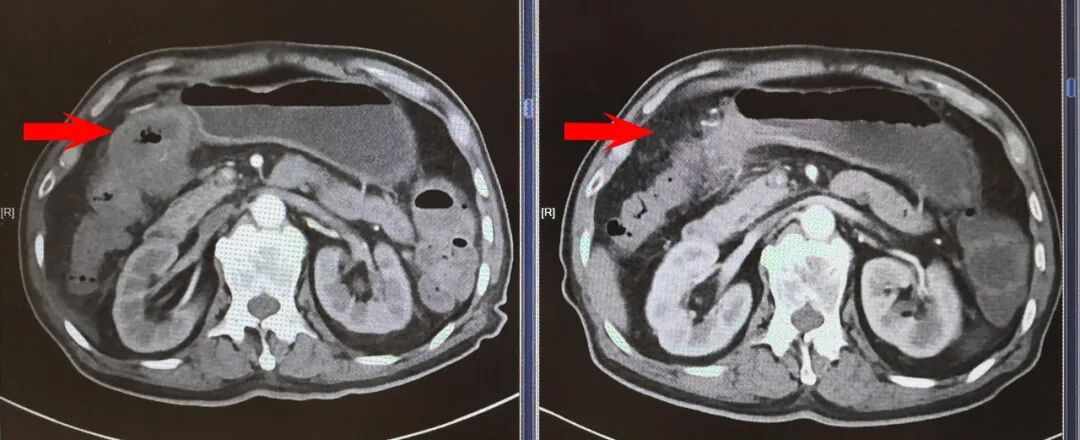

案例一:局部晚期结肠癌患者的重生之路

在过去,一位局部晚期结肠癌患者需要往返多个科室,面对不同建议,耗费数周才能定下治疗方案。而在CCC平台上,这一切变得简单高效:专员负责,次日便组织MDT讨论——放射科重新读片,肿瘤科给出新辅助方案,外科评估手术时机,中医同步调理。一次讨论,方案当场敲定。

图片

▲患者经治疗后,肿瘤明显缩小

三个月后,奇迹发生了:肿瘤明显缩小,手术顺利切除,术后病理显示—病理学完全缓解(pCR),肿瘤细胞完全消失。

患者感叹:“除了配合治疗,我什么都没操心,不用纠结,不用奔波,病就治好了。”